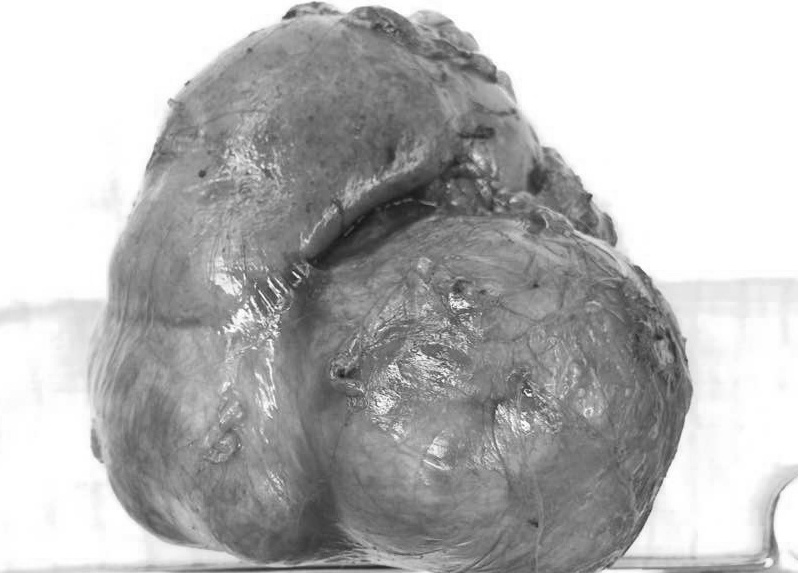

![]() |

| Bướu thận nặng gần 1 kg được lấy ra khỏi người của bà Vy. Ảnh: N.P. |